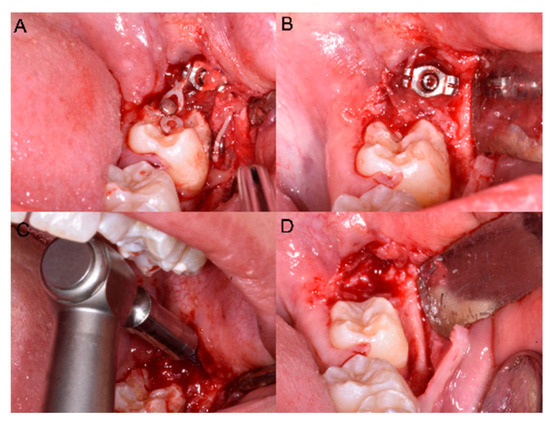

The MM2 was considered upright when the mesial marginal ridge was above the distal contours of first mandibular molar (MM1) (Figure 3).

Figure 3.

Post-treatment panoramic radiograph showing the correct inclination of 3.7 before miniscrew removal.